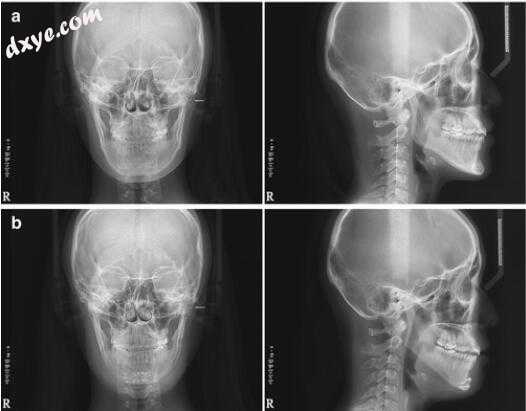

案例1:减少颏成形术一名25岁的女性抱怨长,不对称和预后的下巴(图11.8)。通过使用梯形截骨术减少颏成形术,下巴的长度减少5mm,并且使用预弯曲板进行2mm后退以改善投射。进行额外的固定以确保骨段两端的骨接触(图11.9)。为了防止软组织下垂,使用PDS 3-0进行悬吊缝合。长度明显减少,术后5个月下巴投射得到改善(图11.10)。

8.jpg

图11.8病例1.术前正面(a)和侧面(b)患者的照片

9.jpg

图11.9病例1.术前(a)和术后(b)X线片显示长度缩短和预后改善